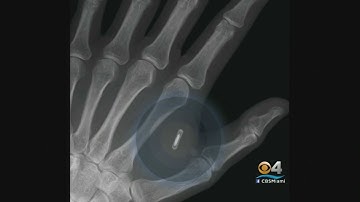

Grindhouse Update - Northstar Implants, Future Grind, Body Hacking Con, & More